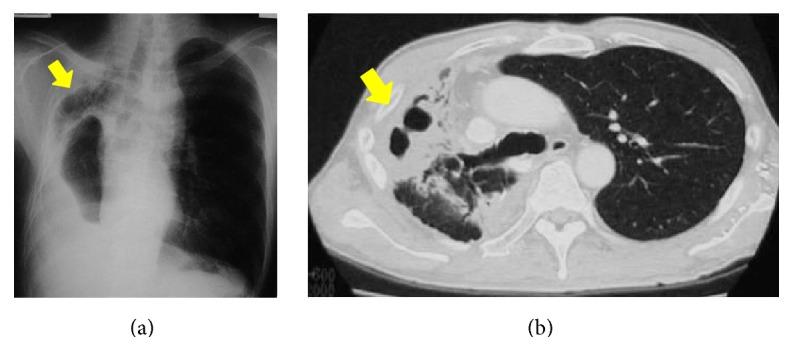

Slow, progressive, and destructive changes in the residual lung after surgery for lung cancer, known as "destroyed lung," are delayed nonrecurrent complications. Destroyed lung can be a difficult condition to treat due to repeated infections and is therefore a complication that should not be ignored. We had three cases of intractable pulmonary aspergillosis difficult to treat associated with destroyed lung, after lung cancer surgery. Two of these patients followed a characteristic clinical course, which started with a cystic change just below the pleura and subsequently led to respiratory failure and death due to repeated infections. The third patient followed a similar clinical course and is currently under regular follow-up. Our cases suggest that concomitant occurrence of severe complications following surgery for lung cancer, such as destroyed lung and pulmonary aspergillosis, should be monitored because these complications can lead to respiratory failure and fatal clinical course. Radical surgery is not possible, especially when medical treatment is ineffective in controlling repeated infections and the patient's general condition is worsened due to prolonged chronic inflammation. Therefore, aggressive surgical intervention should be considered before patients worsen.

肺癌手术后残肺出现的缓慢、进行性和破坏性变化,即所谓的“毁损肺”,属于延迟性非复发性并发症。由于反复感染,毁损肺可能是一种难以治疗的病症,因此是一种不应被忽视的并发症。我们有3例肺癌手术后与毁损肺相关的难治性肺曲霉病病例。其中2例患者呈现出典型的临床病程,始于胸膜下方的囊性改变,随后因反复感染导致呼吸衰竭和死亡。第3例患者有类似的临床病程,目前正在接受定期随访。我们的病例表明,肺癌手术后应监测严重并发症如毁损肺和肺曲霉病的同时发生情况,因为这些并发症可能导致呼吸衰竭和致命的临床病程。尤其是当药物治疗无法有效控制反复感染且患者的一般状况因长期慢性炎症而恶化时,根治性手术是不可能的。因此,应在患者病情恶化之前考虑积极的手术干预。